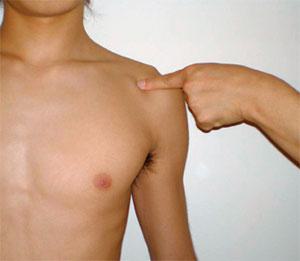

左頸肩腕部の写真を別に示す。指で示している部位はどれか。

1

第一肋骨

2

胸鎖関節

3

肩鎖関節

4

烏口突起

5

上腕骨小結節